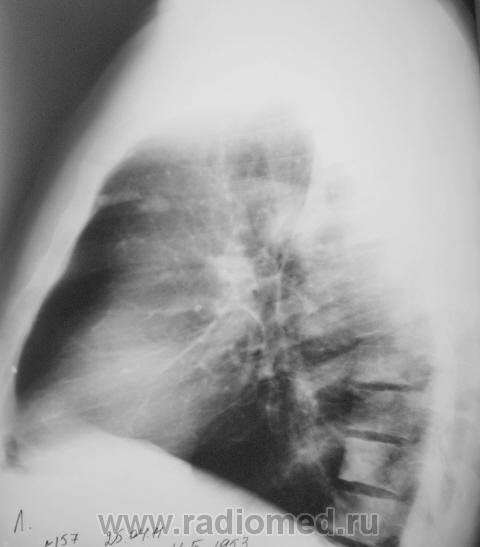

Сделали "томку".

Приложения:

1.p4260045a.jpg2.p4260046a.jpg3.p4260047a.jpg4.p4260048a.jpg5.p4260049a.jpg

Мысль всё о метастазах. Клинических проявлений нет никаких? В брюшной полости ничего не растет?

Мы тоже высказали мнение о наличии метастазов. У пациента установлен ( в области) рак предстательной железы, диагноз в ООД вверифицирован.

Я тоже сразу подумала о мтс и это средостение справа как смещено т.е. л.узлы егосместили?